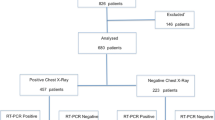

Chest CT and initial virology test results were available for the 694 patients. A flowchart of the study is shown in Fig. 2. Main reasons for admittance together with the COVID-19 relevant symptoms are provided in Table 1. Pulmonary and otolaryngology symptomatology was the main reason for admission at the emergency department for 67% of the patients.